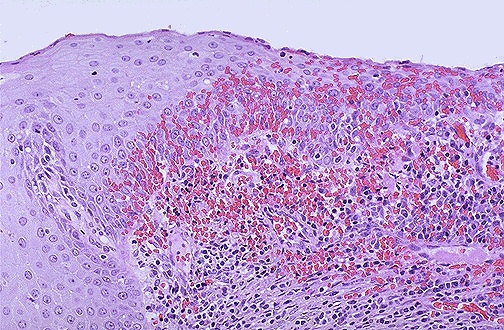

Image 7.2

The low power microscopic appearance of the cervix is shown here.